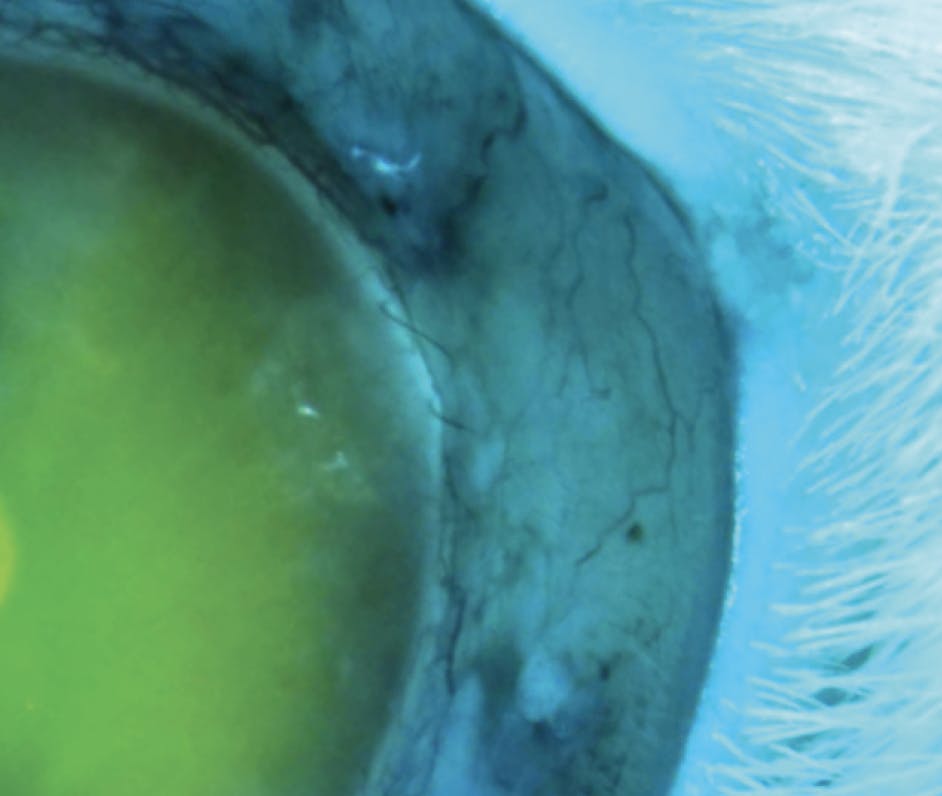

VisiPlate is undergoing early feasibility testing and has been evaluated in multiple long-term (3–6 month) studies using New Zealand white rabbit eyes. In this rabbit model, VisiPlate has been shown to be well tolerated and to reduce IOP.3 The tip of the VisiPlate is positioned in the anterior chamber (Figure 2), where it facilitates aqueous flow through the network of hexagonal microchannels into a low-lying bleb. The bleb has been confirmed with a postoperative injection of fluorescein dye into the anterior chamber, which revealed dispersion to the subconjunctival space (Figure 3). The company continues to validate the performance of VisiPlate in rabbit models, and testing has shown healthy bleb development even without the use of an antifibrotic agent such as mitomycin C.

Figure 3. An injection of fluorescein dye into the anterior chamber of an implanted New Zealand white rabbit on postoperative day 21 ±3 shows the device facilitated dispersion of aqueous humor from the anterior chamber into the subconjunctival bleb.